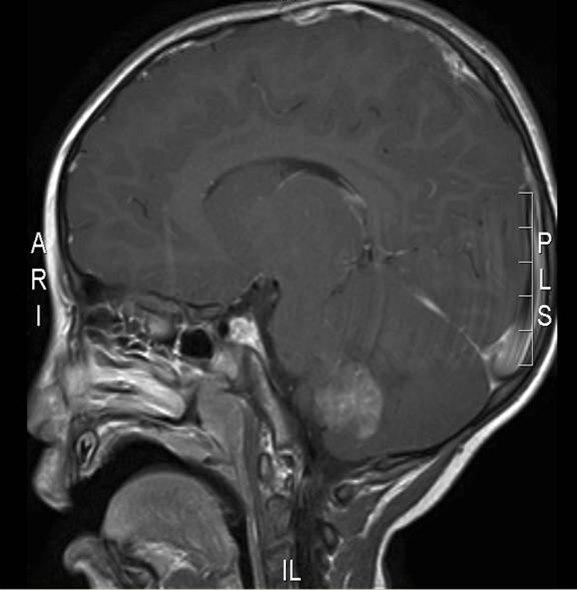

Atypisk teratoid rhabdoid tumor, sagittalt snitt

Gjengitt med tillatelse av Radiologisk avdeling, Universitetssykehuset Nord-Norge